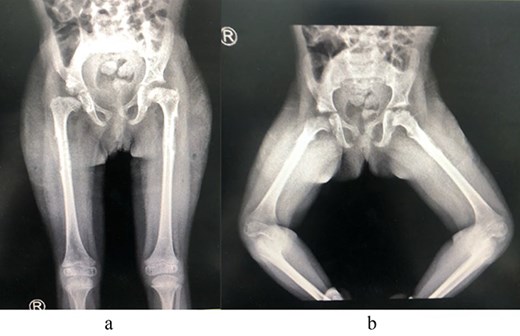

A 2-year-old girl was referred to our pediatric orthopedic clinic at XXX from a peripheral hospital for abnormal gait. On examination, the child had short stature and was thin. She had multiple dysmorphic features, which included a large head with frontal bossing and a triangularly shaped face, mid-face hypoplasia with depression in the nasal bridge and a fleshy nose tip, long philtrum, small pointy chin, micrognathia with large, prominent ears, and lordosis and waddling gait. A focused hip exam revealed bilateral limited hip abduction and leg length discrepancy. Images of the hips showed severe bilateral hip dysplasia (Fig. 1).

(a) Pre-operative AP view of the pelvis showing bilateral DDH. (b) Pre-operative frog-lateral view of the pelvis showing bilateral DDH.